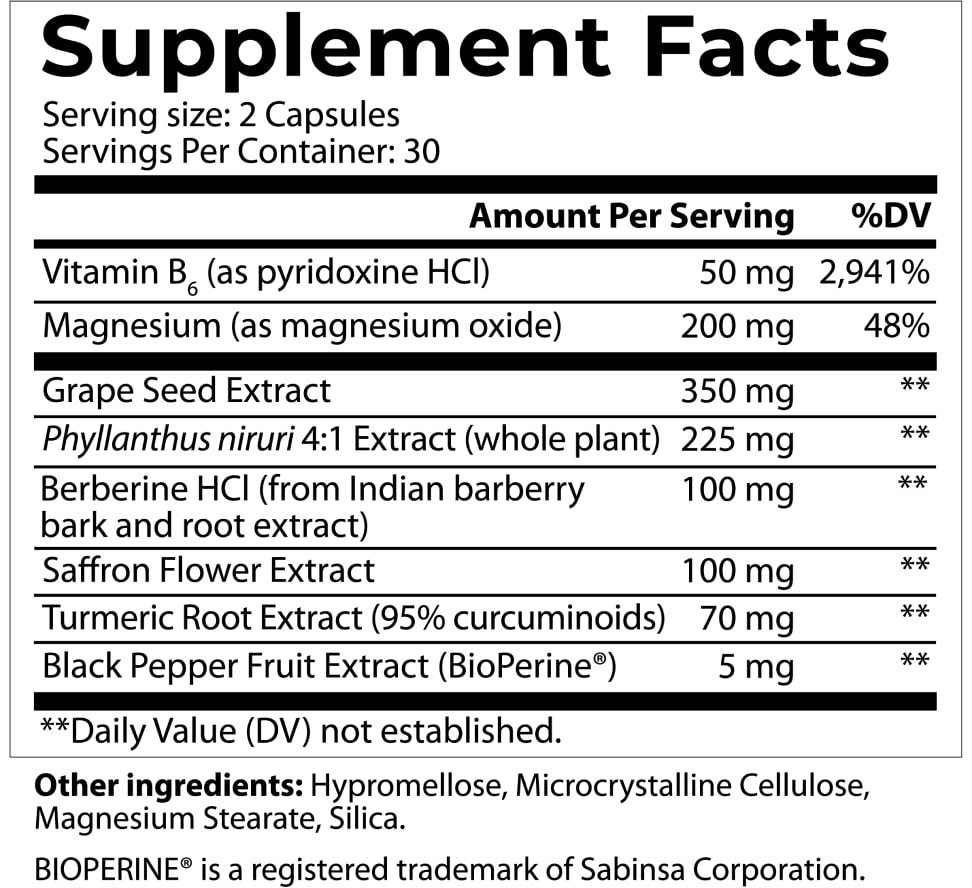

INGREDIENTS:

Vitamin B6

Vitamin B6:

supplementation has been used to lower urine oxalate excretion (the most common cause of kidney stones) in people with elevated oxalate in urine.

In a study of 95 patients with elevated levels of oxalate in their urine were treated with a combination of dietary counseling and Vitamin B6.

75% of patients showed a significant decrease in urinary oxalate excretion and 39% of patients had a decrease from high urine oxalate levels to a normal range of urine oxalate.

Magnesium

Magnesium:

is a mineral everyone is familiar with…but maybe not when it comes to kidney health. Yet, when it is found in higher levels in the body it’s associated with improved survival among chronic kidney conditions (CKD) and end-stage renal disease patients. Optimizing magnesium levels helps delay kidney deterioration in impaired kidneys.

People with kidney problems have increased difficulty flushing Magnesium. So the type and dosage are critical to retaining overall health balance. Magnesium oxide protects against the hardening of arteries, which reduces blood flow to the kidneys and causes further damage. Magnesium oxide has a better outcome on the kidney than other forms.

Grape Seed Extract

Grape Seed Extract:

has been getting a lot of press lately…and for good reason! GSE is a complex mixture containing substances that exhibit multi-organ protection in clinical trials. In a 6-month study, 23 patients with chronic kidney ailments (stage 2-4) were given GSE with their usual medication. GSE showed beneficial effects on kidney function and antioxidant status and it also lowered protein levels in the urine.

Phyllanthus niruri

Phyllanthus niruri:

has also earned the colorful nickname “stonebreaker” for its ability to inhibit the formation of kidney stones caused by oxalate and calcium deposits. Triterpenes found in Chanca Piedra help normalize their concentrations, significantly reducing the likelihood of problematic stones. making them smoother and more fragile.

In 12 week study, 56 patients who had kidney stones were given tea infused with Chanca Piedra extract. It significantly normalized uric acid and oxalate levels and reduced the number of stones in 67.8% of the patients..

Berberine HCl

Berberine HCl:

reduces blood sugar, cholesterol, triglycerides, inflammation, and oxidative stress and improves heart markers. Each benefit supports healthy kidney functions. Studies also show Berberine significantly improves kidney damage markers and renal blood flow and protects against toxicity.

In a 24-month-long study, 69 hypertensive patients with Type II sugar disorders received a dose of berberine along with their usual medication.

After treatment, patients in the berberine group exhibited significant reductions in renal damage markers and improved renal blood flow, inflammation, and oxidative stress.

Saffron Flower Extract

Saffron Flower Extract:

is much more than a tasty cooking herb! It’s also effective in the battle against wayward blood fats and high blood pressure. A total of 25 preclinical studies reported kidney protective effects of saffron against kidney-toxic drugs and toxins vs the control group.

But perhaps saffron’s most significant “superpower” has to do with blood force through the veins and arteries. In a study of 80 patients with disordered blood sugar saffron’s effect on systolic numbers, and renal, and liver function was tested. After 12 weeks of daily supplementation of saffron powder, a significant change was observed in systolic numbers.

In a systematic review of saffron’s effect on blood force numbers in adults, findings revealed that saffron supplementation has a small but significant effect on improving systolic blood.

Turmeric Root Extract

Turmeric Root Extract:

is a well-known kidney superstar! Curcumin is the active ingredient in turmeric (a traditional herbal remedy & dietary spice). Curcumin can modulate various body substances positively affecting inflammation and oxidative stress.

In one study of 40 patients with reduced kidney function caused by type 2 blood sugar issues, the effects of turmeric on the amount of protein excreted in the urine was reduced significantly.

Another clinical trial examined the effect of oral curcumin supplementation on patients suffering from autoimmune responses affecting kidneys. In a study of 24 patients for 3 months a dose of turmeric root was administered.

A significant decrease in urinary protein excretion, systolic blood pressure, and hematuria (blood in urine) was found when compared to a trial group.

Black Pepper Fruit Extract

Black Pepper Fruit Extract:

is a common kitchen spice that may seem like an odd ingredient for a kidney support formula, but black pepper has one unusual quality that earned it a place here. Black pepper extract increases the absorption of turmeric/curcumin tremendously! This dramatically enhances the impact curcumin has on your kidney health.

Vitamin B6: Clinically proven to have potential for lowering urine oxalate excretion—the most common cause of kidney stones. In a groundbreaking study of 95 patients with elevated oxalate levels, 75% showed significant decrease in urinary oxalate excretion, and 39% returned to normal range after treatment.

Magnesium: A critical mineral for kidney health, associated with improved survival among serious kidney conditions. This specific form—magnesium oxide—could protect against arterial hardening and has shown better kidney outcomes than other magnesium forms.

Grape Seed Extract: A powerful antioxidant complex showing remarkable results in clinical trials. In a 6-month study with 23 chronic kidney patients (stages 2-4), GSE demonstrated significant benefits for kidney function, antioxidant status, and reduced protein levels in urine when combined with standard medication.

Chanca Piedra Extract: Known as the "stonebreaker" for its remarkable ability to inhibit kidney stone formation from oxalate and calcium deposits. In a 12-week study with 56 kidney stone patients, this extract normalized uric acid and oxalate levels, reducing stones in 67.8% of participants.

Berberine HCl: A comprehensive kidney supporter that could help maintain healthy blood sugar, cholesterol, and defend against pro-inflammatory activity, and oxidative stress. In a 24-month study with 69 hypertensive patients, berberine significantly improved kidney damage markers, renal blood flow, and protected against toxicity.

Saffron Flower Extract: More than just a culinary spice, saffron shows powerful kidney-protective properties. Demonstrated in 25 preclinical studies to guard against kidney-toxic drugs and toxins. A 12-week study with 80 patients showed significant improvements in systolic numbers and renal function.

Turmeric Root Extract: A renowned kidney superstar that could modulate pro-inflammatory activity and oxidative stress. Clinical studies with 40 patients showed significant reduction in urinary protein excretion. Another 3-month trial with 24 patients demonstrated decreased blood in urine and improved blood pressure.

Black Pepper Extract: A critical absorption optimizer that could dramatically increase turmeric's bioavailability, maximizing its kidney-protective benefits. This patented form ensures optimal absorption of key nutrients.

We're committed to improving our formulas based on the latest research, which can affect serving size and cause slight variations in ingredients. Depending on the batch, the number of capsules per bottle may vary due to seasonal changes in the density of natural ingredients, affecting the space the nutrients occupy. Despite these variations, each version supports the same health and wellness benefits. There may be brief delays in website updates, so please refer to the product label for the most accurate information.